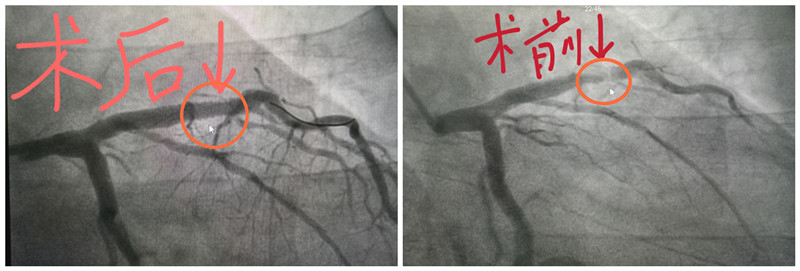

15:55 通过冠脉造影,心内科主任阮宏标发现患者冠脉前降支近段狭窄已达99%,几乎是完全闭塞,血流中断造成了此次心肌梗死。

16:15 导丝通过闭塞血管,植入前降支支架,血流得以恢复。